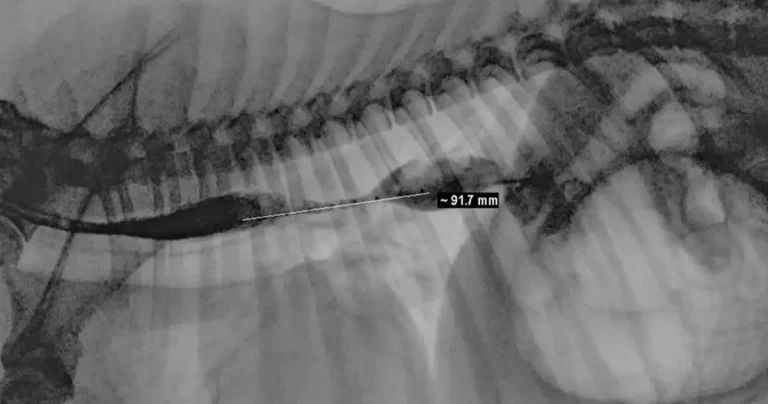

Colt's xray with the stricture measurement.

Colt, a two-and-a-half-year-old Labrador, was fitted with an oesophageal balloon dilation feeding tube (B-tube) at the University of Edinburgh’s Hospital for Small Animals after being diagnosed with a 9cm stricture.